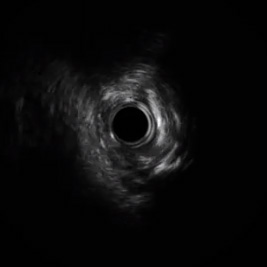

• La ecografía intravascular mostró un vaso muy estrecho con placa fibrocálcica considerable. A causa de estos hallazgos, se tomó la decisión de proceder con el Rotablator.

• Una ecografía intravascular mostró una subexpansión en la parte proximal del stent.